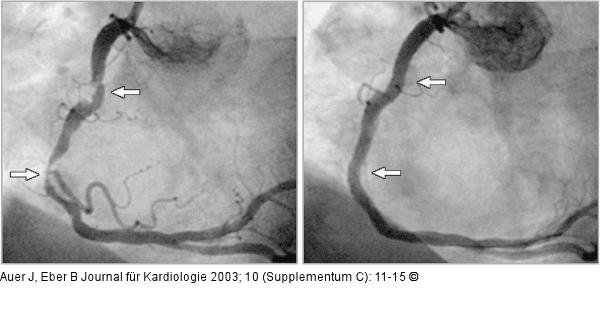

Abbildung 4: Koronarangiographie - Stenose - Stent Links: Selektive Koronarangiographie mit Darstellung zweier Stenosen in der rechten Herzkranzarterie; Rechts: Selektive Koronarangiographie - Kontrollangiogramm nach PTCA (perkutane transluminale Koronarangioplastie) und Stentimplantation indie Stenosen in der rechten Herzkranzarterie |